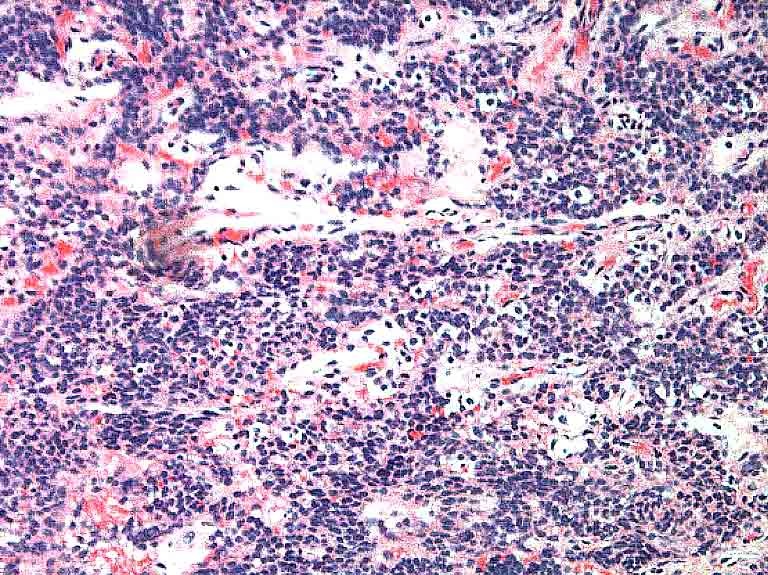

This revealed total occlusion of the right mainstem bronchus with pink-colored

granulation tissue. The tissue was friable and bled easily with the biopsy.

The biopsy was 'typical' for this disease.

ENLARGE a low power magnification of the biopsy.